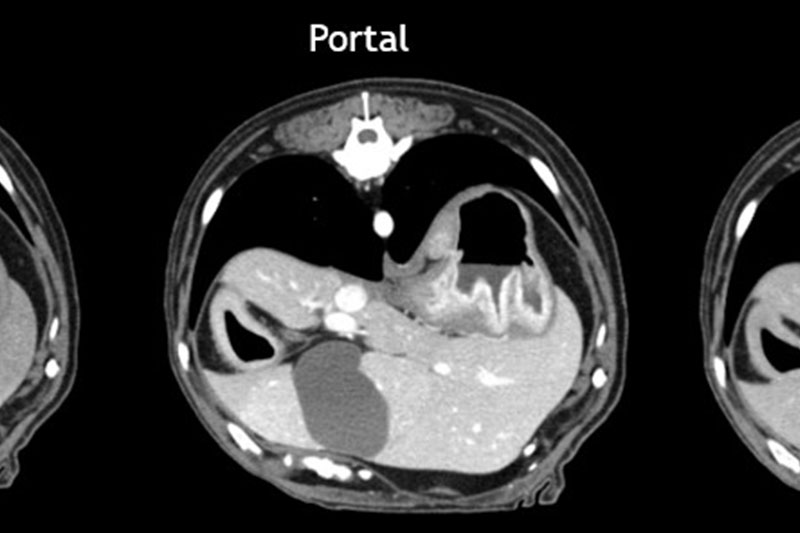

| 복부 | 간, 비장, 신장, 위장관 종양 및 결석, 부신, 림프절 등 |

혈관 조영(Angio CT)을 통한 혈관 이상 진단

복부 장기의 종양, 염증, 결석, 기형 등 고해상도 분석